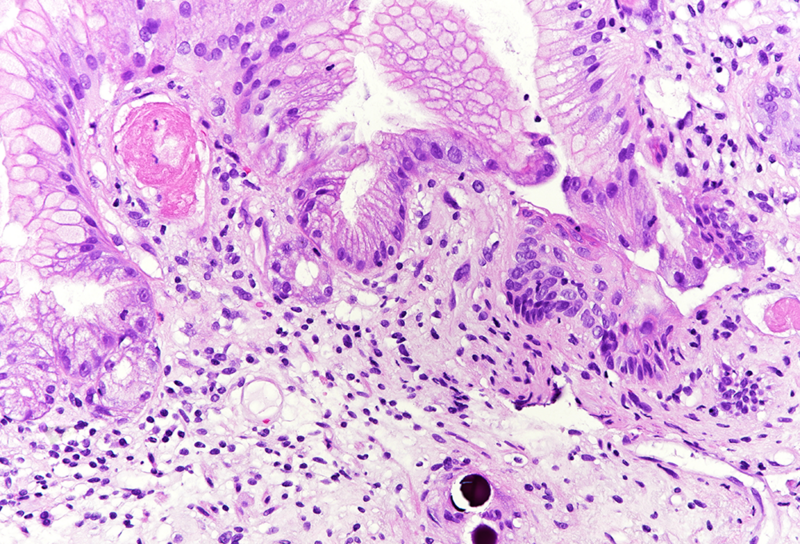

Histologically, in the duodenal bulb and all gastric biopsies was visible a blueish spherical foreign material in the stroma, inside small blood vessels, which corresponded to the given chemoembolization medium – yttrium-90 microspheres. Surface mucosa of all samples showed reactive and inflammatory changes with atrophic areas (Panels A-D).

Selective internal radiation therapy (SIRT) is increasingly used for the treatment in non-resectable primary or secondary liver malignancies by injecting intra-arterially radioactive yttrium-90 microspheres. However, due to rich vascularisation of the liver and surrounding organs, migration of microspheres is possible, leading to complications. The most common complications are involving GI tract – gastritis, gastrointestinal ulcers, cholecystitis and liver disease, and non-GI - radiation pneumonitis. That is why awareness of these complications and multidisciplinary approach are necessary for patient’s overall well-being. The pathophysiological mechanism behind gastric injury is not fully understood, but seems to be due to chronic and persistent ischemic injury to the mucosa of the stomach, leading to ulceration and inflammation in the viable mucosa. Please note that reactive cytological and nuclear changes may be marked, thereby mimicking dysplasia (a dangerous caveat).